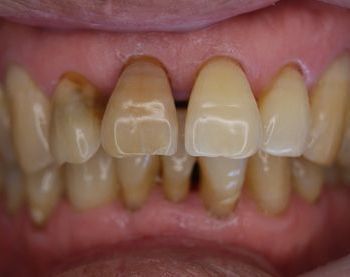

フィステル(瘻孔)があって、変色している症例。根管治療をすると、フィステルは消失。

DSC00513.JPG

DSC00520.JPG

レントゲン写真がこちら。根管治療&根管充填(この場合キャナルス&ガッターパーチャ)後。

で、漂泊してCR充填すればきれいに出来上がり。